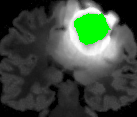

To emphasize the interest of our method, we propose a framework to perform fast segmentation and labeling from an image database. SuperPatchMatch is well adapted to deal with huge and constantly growing databases since no learning phase is required, contrary to most existing approaches based on supervised machine learning [17, 18], or recent neural network methods [19, 20]. We apply SuperPatchMatch to the challenging Labeled Faces in the Wild (LFW) database [21], where the goal is to extract hair, face, and background within images decomposed into superpixels, and to the segmentation of tumors on non-registered Magnetic Resonance Images (MRI). Finally, SuperPatchMatch outperforms, in terms of computational cost and accuracy, state-of-the-art methods.

To demonstrate the interest of the superpatch structure and the SPM algorithm, we adapt our approach to exemplar-based labeling. We consider two experiments: face labeling on the LFW dataset [21], and segmentation and labeling on non-registered medical images from the BRATS dataset [49].

V-C Non-Registered MRI Segmentation Experiments

To demonstrate the robustness of the superpatch structure and the proposed framework, we apply SPM to brain tumor segmentation on multi-modal non-registered Magnetic Resonance Images (MRI). Classical patch-based and multi-atlas structure segmentation methods are based on registered subjects. Consequently, they cannot be efficiently applied in this non-registered context, due to the substantial variation in tumor shape and locations. Superpixels enable to better capture the tumor geometry, thus increasing the segmentation accuracy. Superpixel and supervoxel-based approaches have been applied to tumor segmentation [54]. However, in this work, the neighborhood is not considered and the ANN search is exhaustive, and computed on a large multi-modal histogram descriptor, leading to prohibitive computational time.

SPM can be efficiently applied to tumor segmentation since it quickly finds good correspondences without image registration, and uses the superpixel neighborhood to improve the matching. In this application, the segmentation is computed from a superpixel decomposition [1], then each region (tumor or background) is labeled with SPM.

We present results obtained on the MICCAI multi-modal Brain Tumor Segmentation (BRATS) dataset [49]. This challenging dataset contains real and simulated patient data, with overall poor resolution and large variation of tumor shape and position. For both types, high grade (HG) and low grade (LG) tumors are provided with four modalities: T1, contrast enhanced T1 (T1C), T2, and FLAIR. Overall, there are 20 and 10 real patient data with respectively HG and LG tumors, and 25 images for both HG and LG simulated tumor data. We use the same SPM parameters as in Section V-B, taking a multi-modal histogram, containing the levels of gray intensity on all MRI modalities as descriptor for superpatch matching, and performing the regularization (8) at the pixel scale to compare with pixel-wise ground truths. Each subject is segmented by the remaining of its type in a leave-one-out procedure.

In Fig. 12, we show several tumor segmentation results for all data types.

In Table II, we compare results obtained using different descriptor structures:

patch-based [48], superpixel-based [54],

and superpatch-based (= pixels).

We use the Dice coefficient [55] as evaluation metric,

measuring the overlap between the automatically segmented structure and the ground truth.

The superpixel-based approach

appears very limited since it fails at capturing the tumor context and their location in other images.

Regular patches are also limited in this context, due to the variations in the structure shapes.

Superpatches provide a robust descriptor, since they follow image intensities and capture the superpixel neighborhood,

leading to more accurate segmentation.

These experiments demonstrate that superpatches within the SPM framework provide fast and accurate segmentation results

even on non-registered multi-modal images with poor resolution.